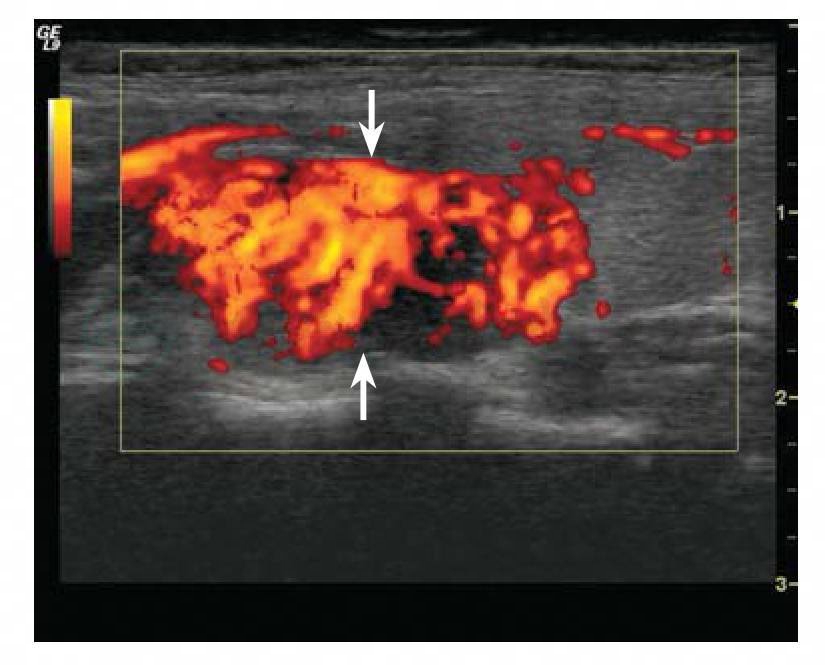

2.彩色/能量多普勒超声

肿瘤前缘常有明显的血管绕行(实为甲状腺被膜血管),可测出动脉频谱,并可见多条动脉分支进入瘤体内(图4-3),内部一般可见丰富的血流信号(图4-4)。有时可显示腺瘤的蒂部。

图4-4 甲状旁腺腺瘤彩色血流图

箭所指肿瘤内部可见丰富的血流信号